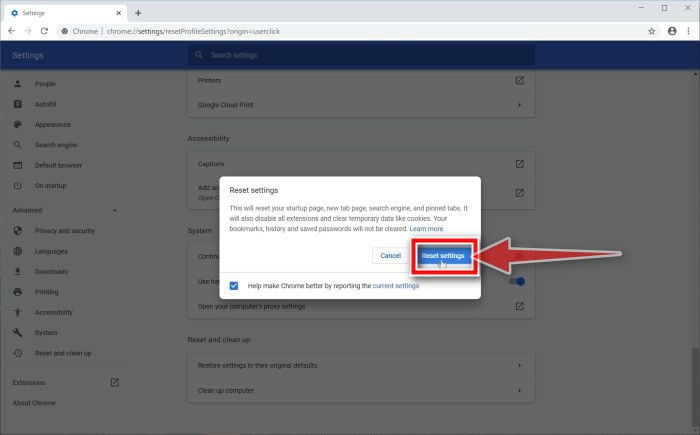

#Simple suture with omental patch Patch

The surgical treatment with a simple omental patch closure of the perforation has not changed much over a century and PPU still remains a life-threatening condition with a high mortality of up to 40% being reported ( 8).